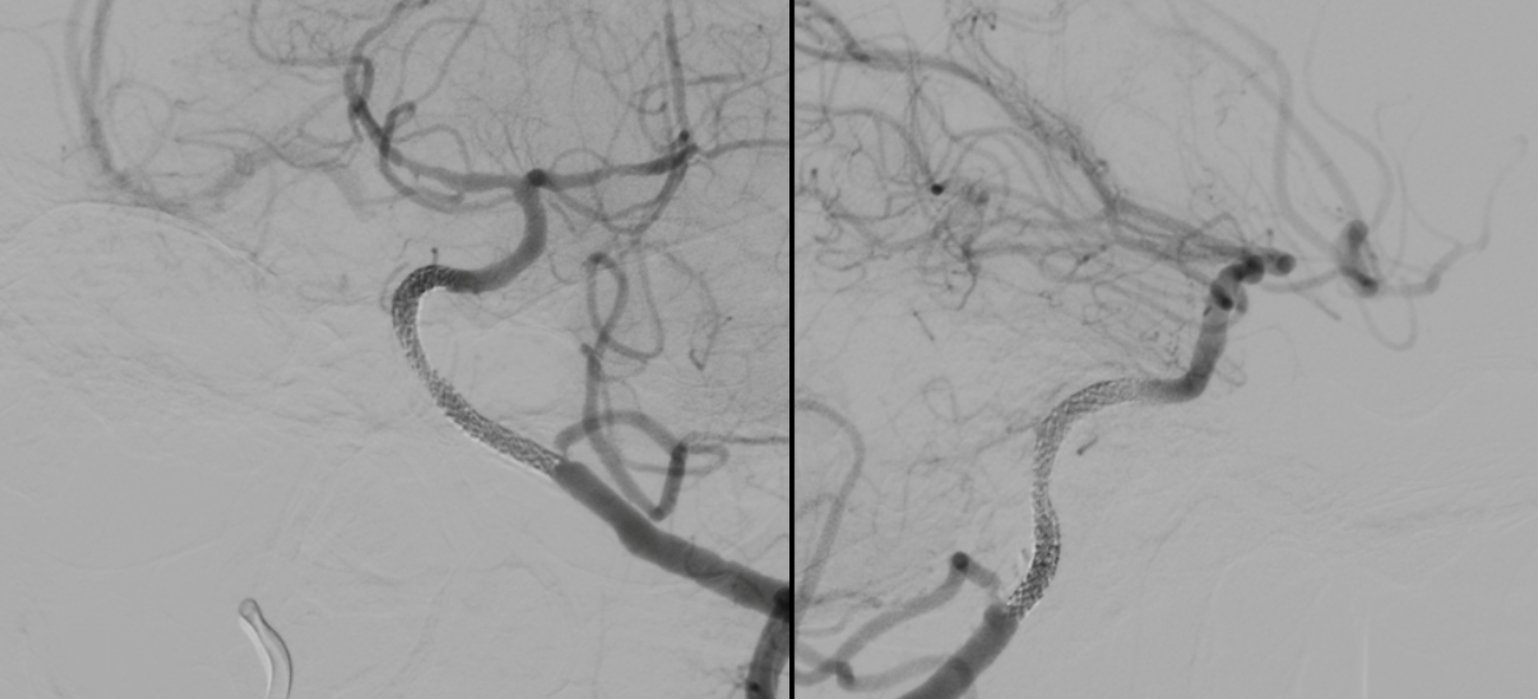

Back with a vengeance

At first wire goes into subintimal channel — see how it stays on the side and does not advance in the movie below?

Now the good way

Once you are through, follow the wire with microcatheter, replace wire with snare, catch the wire coming up from below, and bring it up through the stenosis… sounds easy, huh…

Now, image through a microcatheter from below

Stenting. Lots of calcs